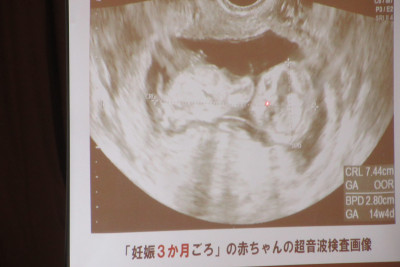

本日午後、印西市子ども家庭課の助産師の方を講師にお招きし、「性に関する指導」を行いました。

赤ちゃん人形を抱っこする体験を通して、改めて生命の誕生や成長について学びました。